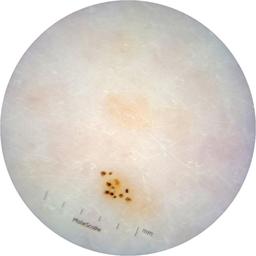

ISIC_6363669

Information

923 x 923

Clinical

Field Value

acquisition_day 264

age_approx 65

anatom_site_1 Trunk

anatom_site_2 Anterior trunk

anatom_site_general anterior torso

concomitant_biopsy False

diagnosis_1 Benign

diagnosis_confirm_type single image expert consensus

family_hx_mm True

image_manipulation instrument only

image_type dermoscopic

lesion_id IL_2591344

patient_id IP_1322385

personal_hx_mm True

sex female